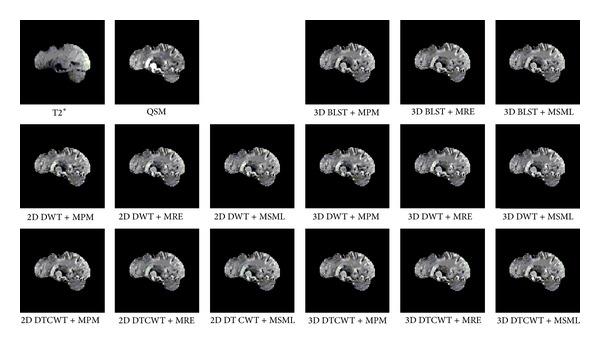

Nowadays many MRI scans can give 3D volume data with different contrasts, but the observers may want to view various contrasts in the same 3D volume. The conventional 2D medical fusion methods can only fuse the 3D volume data layer by layer, which may lead to the loss of interframe correlative information. In this paper, a novel 3D medical volume fusion method based on 3D band limited shearlet transform (3D BLST) is proposed. And this method is evaluated upon MRI T2* and quantitative susceptibility mapping data of 4 human brains. Both the perspective impression and the quality indices indicate that the proposed method has a better performance than conventional 2D wavelet, DT CWT, and 3D wavelet, DT CWT based fusion methods.

如今,许多磁共振成像(MRI)扫描可以提供具有不同对比度的三维体数据,但观察者可能希望在同一三维体中查看各种对比度。传统的二维医学融合方法只能逐层融合三维体数据,这可能导致帧间相关信息的丢失。本文提出了一种基于三维带限剪切波变换(3D BLST)的新型三维医学体融合方法。并根据4个人脑的MRI T2*和定量磁化率映射数据对该方法进行了评估。视觉印象和质量指标均表明,该方法比传统的基于二维小波、双树复小波变换(DT CWT)以及三维小波、DT CWT的融合方法具有更好的性能。